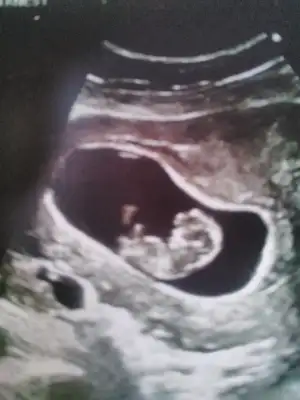

Kizlar nub bilen varmı sizce kızmı erkek mi IMG_20181115_164559.webp